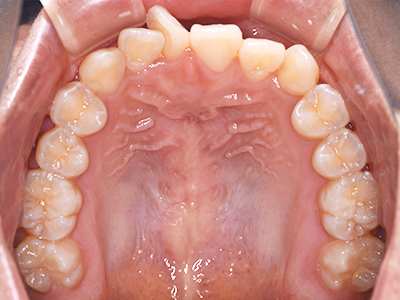

歯並びの相談に来られるお子様は、口呼吸をしているケースが多く、これが歯並びに大きな影響を与えています。

- 口呼吸をしている

↓ - 舌の位置が悪くなる

↓ - 頬の圧力が上の歯列にかかりやすくなる

↓ - 上あごが狭くなる

↓ - 下あごが狭くなる・下あごの位置が悪くなる

↓ - さまざまな不正咬合が生じる

ないき歯科クリニックでは、上あごの成長不足を補い、鼻呼吸を獲得しつつ歯列を整え、将来のお口をより健康な状態にすることをゴールに定める矯正治療をおこなっています。